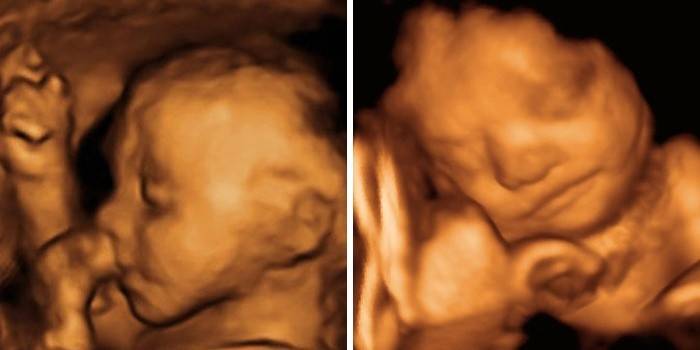

W tym tygodniu ciąży płód wzrośnie do 34–35 cm i waży około 650–660 g. W miarę wzrostu dziecka staje się ono bardziej zatłoczone w jamie macicy, a jego ruchy stają się silniejsze i bardziej namacalne. Stopniowo dziecko będzie zajmować pozycję głową w dół, dociskając ręce i nogi do ciała (pozycja embrionalna). Teraz ruchom dziecka towarzyszy widoczne napięcie i zmiana brzucha, okresy, w których widać kontury kończyn, a ruchy nóg pod żebrami mogą być nawet niewygodne. Teraz musisz zwrócić uwagę na aktywność płodu - jeśli dziecko jest ciche lub nadmiernie aktywne przez długi czas, powinieneś skonsultować się z lekarzem, aby wykluczyć jego głód tlenu. Około cztery ruchy na godzinę lub więcej niż 10 ruchów dziennie uważa się za normalne.

Do tego czasu hemopoeza dziecka jest prawie ukończona, a szpik kostny dziecka aktywnie uczestniczy w wytwarzaniu wszystkich komórek krwi. Pozwala to na poprawę układu odpornościowego płodu - limfocyty i leukocyty są szkolone do walki z infekcją w przyszłości. W tej chwili, zgodnie z USG, płeć dziecka jest wyraźnie określona i już wiesz, na kogo czekasz - chłopca lub dziewczynkę. W tym czasie jądra chłopca zaczynają opadać do moszny, u dziewcząt dochodzi do tworzenia się pochwy.

Teraz narządy zmysłów dziecka są już dobrze rozwinięte - słyszy dobrze, a jego siatkówka może reagować na światło. Dzieciak będzie aktywnie odczuwał ostre dźwięki ze świata zewnętrznego, drżące lub zamrażające. Teraz jego ruchy są coraz bardziej skoordynowane, wykazuje pewną zręczność - dotyka ścian macicy, chwyta pętlę pępowiny, wkłada palce do ust, czuje twarz i ciało. W tym okresie w mózgu pojawia się zakładka wiodącej ręki - niezależnie od tego, czy dziecko będzie praworęczne, czy leworęczne.

W tej chwili płód zwykle zajmuje już pozycję taką, jaka będzie podczas porodu, głową w dół, ale jego pozycja nie jest jeszcze stabilna. Jeśli płód znajduje się z opuszczonymi pośladkami, mogą być wymagane specjalne kompleksy gimnastyczne, aby do okresu 32-34 tygodni odmówił. Mózg dziecka waży już 100 g, wykrywane są okresy zwiększonej aktywności niektórych centrów mózgu, rozwija się rytm snu i czuwania, ponieważ często okresy snu i aktywności płodu nie pokrywają się z czasem matki. Dziecko może aktywnie poruszać się w czasie odpoczynku i snu, a teraz dziecko będzie miało czkawkę częściej, z tego powodu trenowane są mięśnie oddechowe i przepona. Przełyka płyn owodniowy, a specjalne nerwy tworzące czkawkę są podrażnione. To nie jest oznaką patologii - nie powinieneś się martwić.